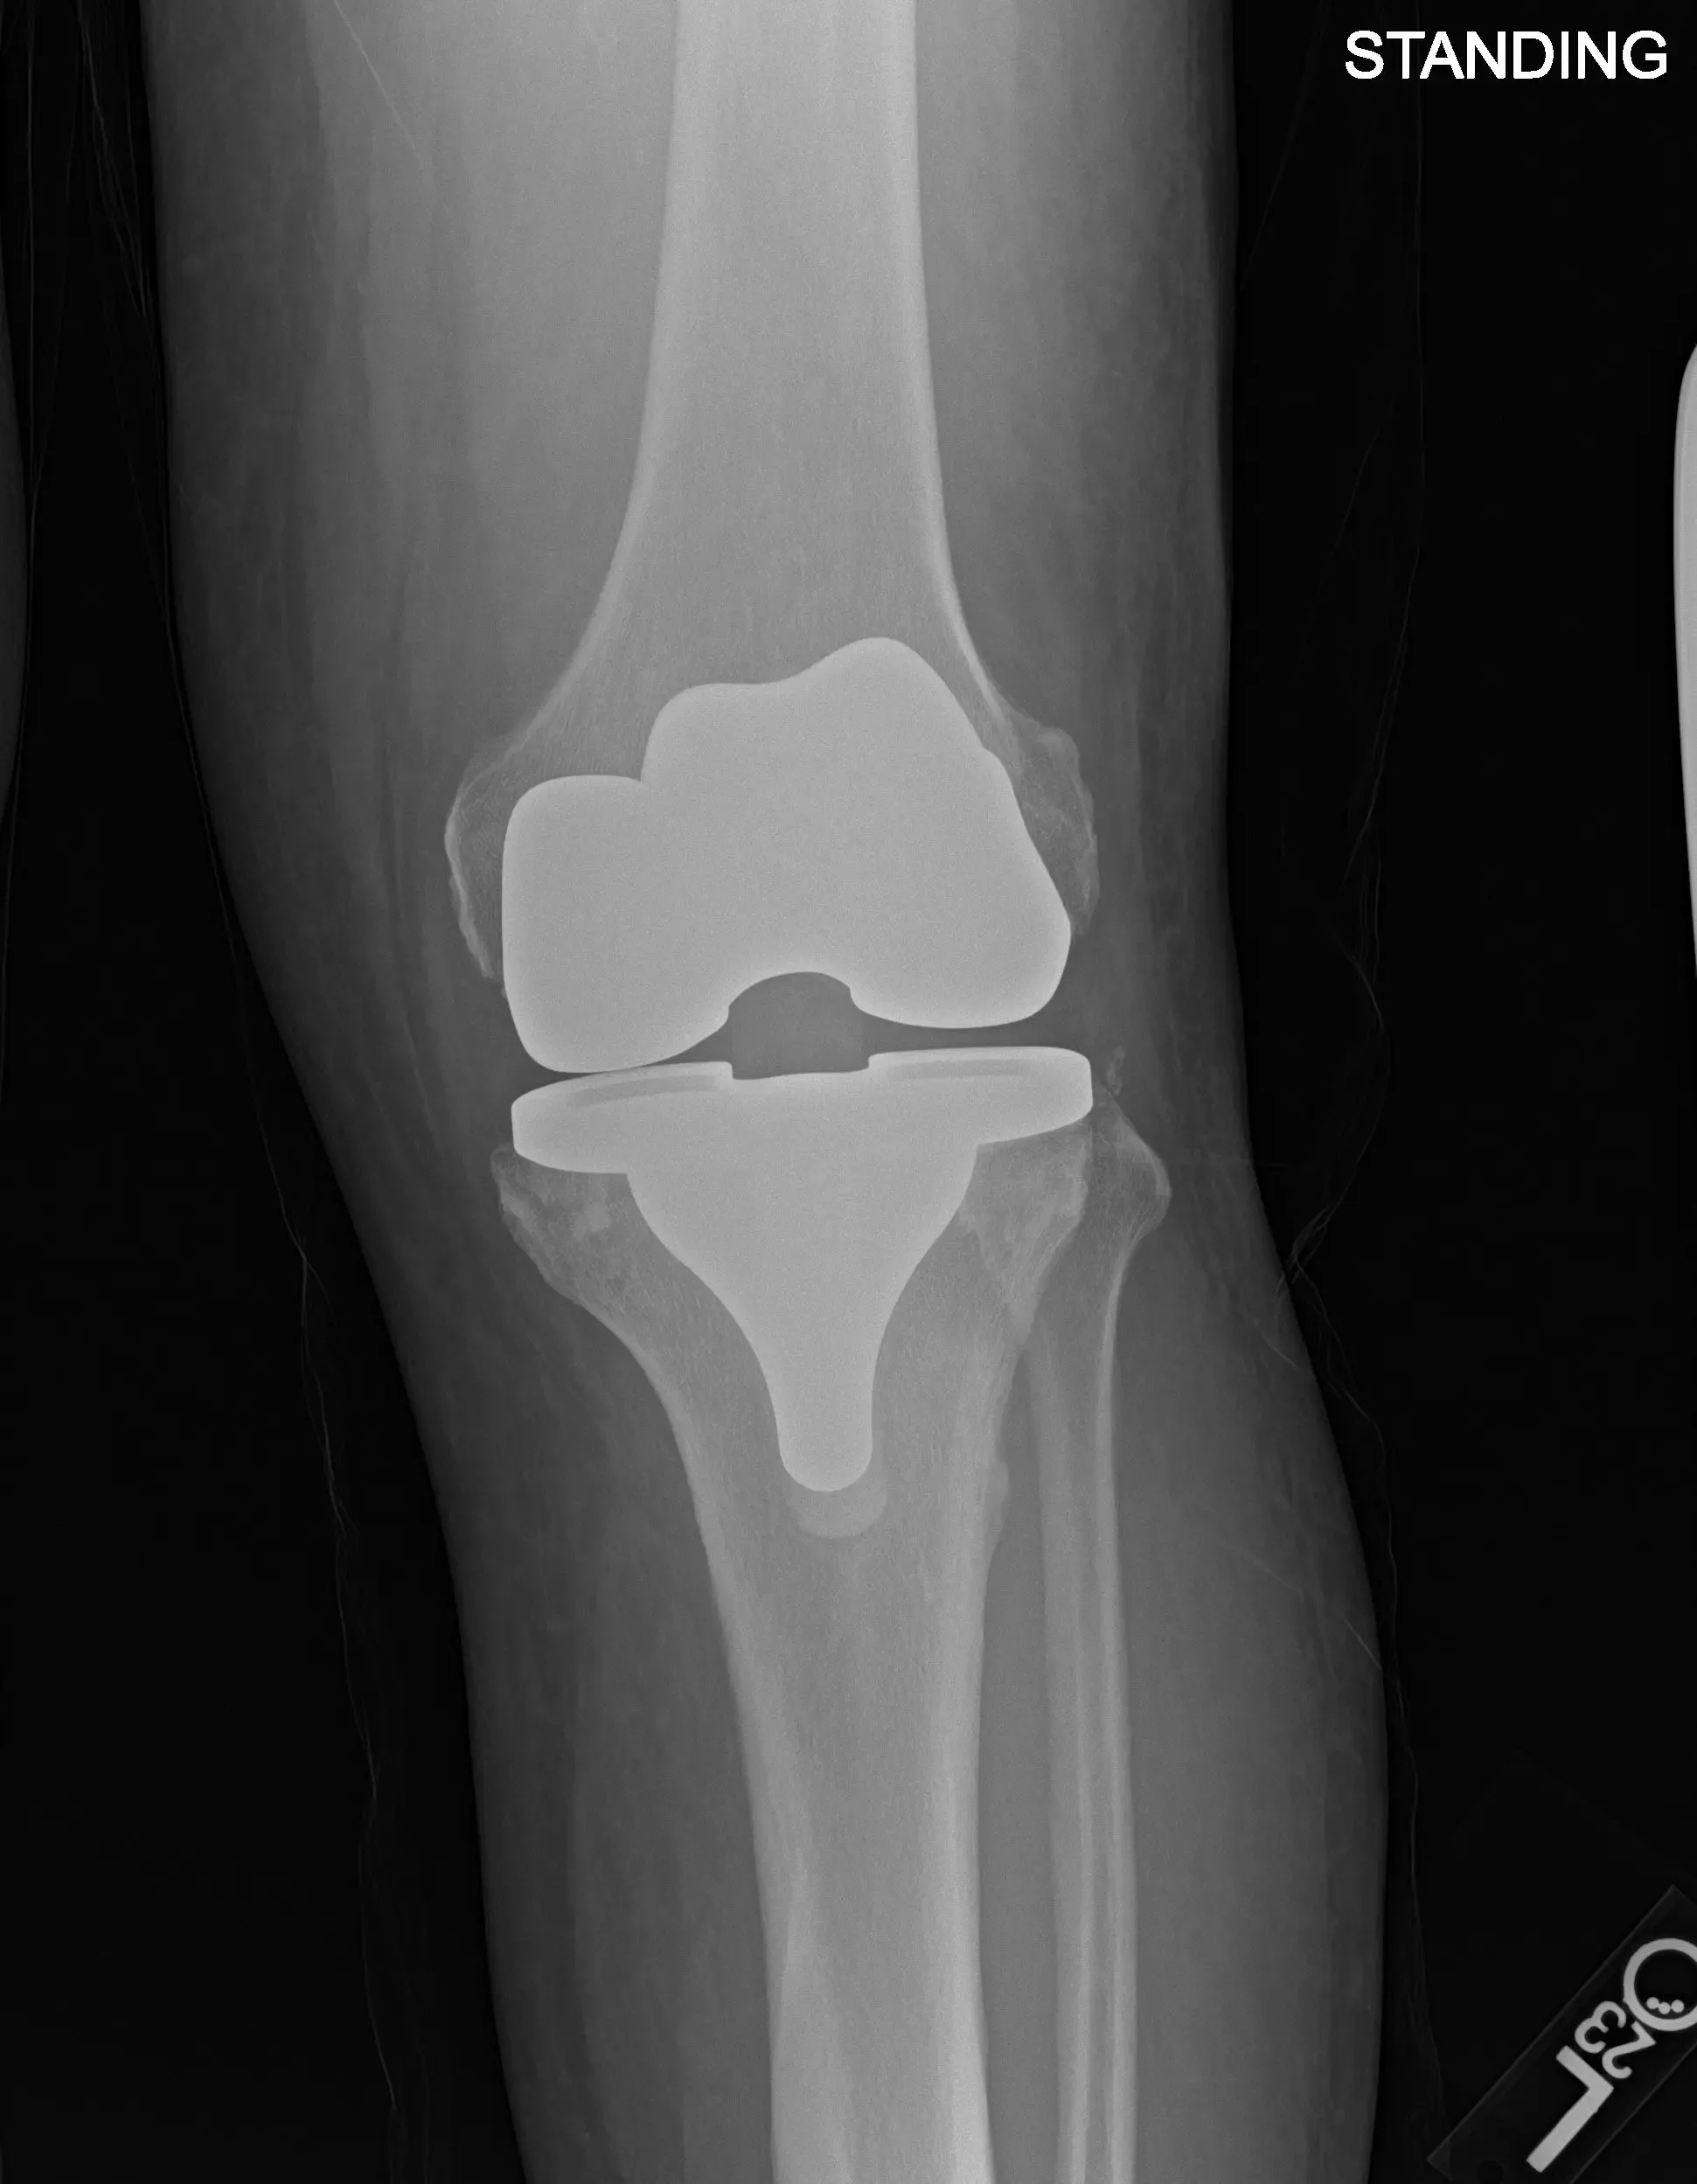

Postoperative X-ray images showing AP and lateral views of the left knee.

Implant used: Custom femoral implant with a custom tibial tray, with 8-mm polyethylene insert, with custom 32-mm x 6-m patellar implant.